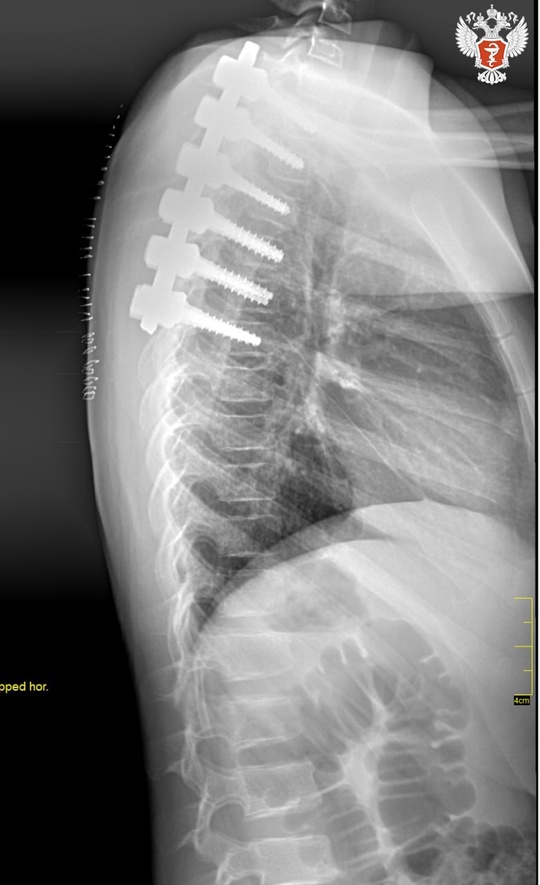

📋 Врачи стабилизировали позвонки при помощи специальной металлической конструкции. В будущем, когда имплантат выполнит свои функции, врачи удалят его.